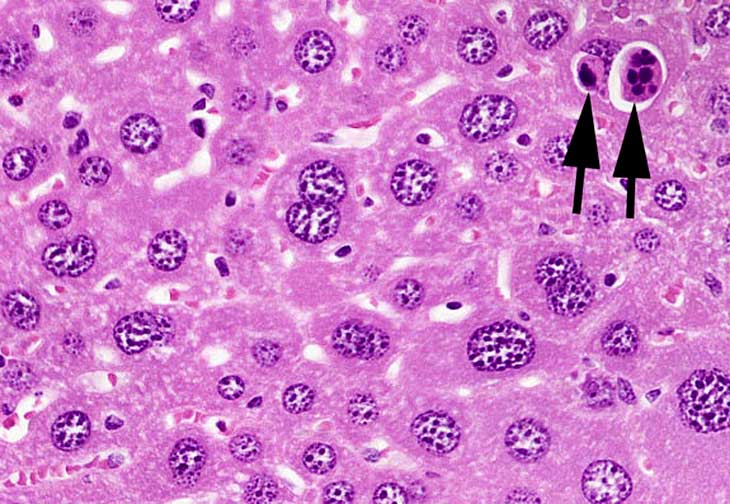

Hepatocytomegaly and karyomegaly with apoptotic bodies (arrows).